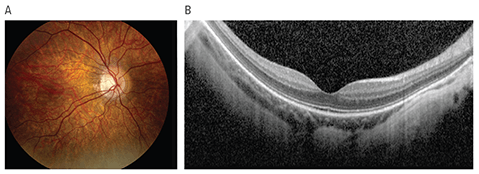

Complete congenital stationary night blindness (cCSNB) is a rare inherited retinal disease that inhibits normal rod cell response to light. Those affected often also have reduced visual acuity, near-sightedness, eye misalignment (strabismus) and involuntary eye shaking (nystagmus).

But in some cases, the classic night blindness (nyctalopia) symptoms do not appear during early childhood, which can mask the condition. Now a study led by Virginia Miraldi Utz, MD, along with colleagues at the University of Iowa, explores the progression of cCSNB associated with variations in the gene TRPM1, one of several known to be linked to the condition.